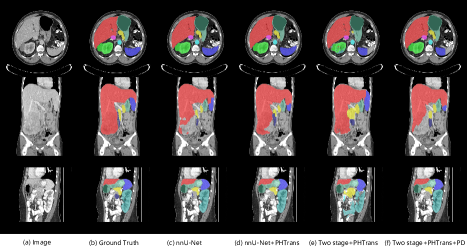

4.2 Qualitative results on validation set

Refer to caption

Figure 3: Visualization of segmentation results of abdominal organs.

We visualize the segmentation results of the validation set. The representative samples in Figure 3 demonstrate the success of identifying organ details by TPP, which is the closest to the ground truth compared to other methods due to retaining most of the spatial information of abdominal organs. In particular, it outperforms TP significantly by leveraging unlabeled data, which enhances the robustness of the segmentation model. Furthermore, we show representative examples of poor segmentation, as shown in Figure 4. The first row demonstrates that TP and TPP only detect part of the spleen (blue region), which can be inferred from the flat edge on the right that the first-stage coarse segmentation did not accurately locate the entire abdominal organ. The second row shows a case with a large tumor inside the liver (red region), where the pathological changes pose an extreme challenge for the abdominal organ segmentation. In this case, nnU-Net shows poor segmentation performance. PHTrans improves this result with the global modeling capabilities of the Transformer. In contrast, benefiting from the strategy of whole-volume based input, TP segments a relatively complete liver. However, the performance of TPP to segment livers with pathological changes degrades when training with more pseudo-labeled data. We consider that pseudo labels generated by training on labeled data without liver disease tend to produce a large amount of erroneous label information in liver disease cases, resulting in a degraded performance of TPP for segmenting liver disease cases. The third row shows another case where none of the methods accurately detected the duodenum (blue-black region).